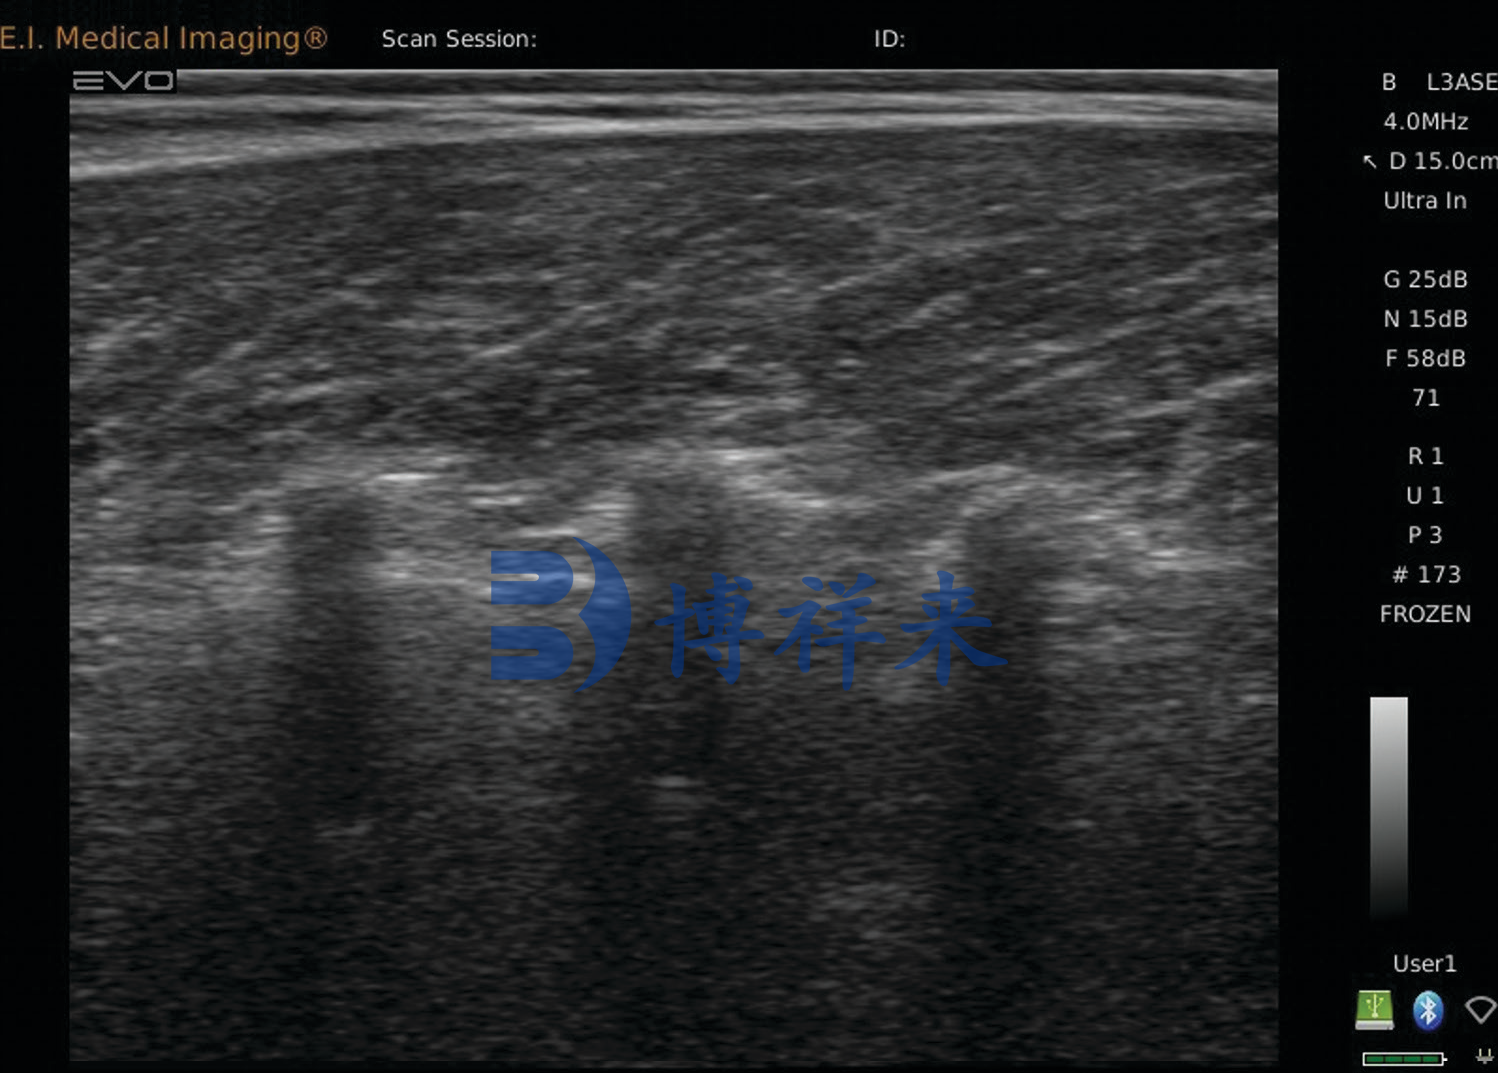

如今,通过背膘眼肌测定仪获取的眼肌横截面图像,不仅能显示眼肌的面积和形状,还能通过图像颗粒度判断脂肪沉积情况。随着AI影像分析的发展,这种判断甚至可以量化为“脂肪评分”,帮助育种人员快速锁定潜力牛只。

超声图像中的肌内脂肪表现为亮点状、网状或条带状的高回声区。AI系统能从中分析脂肪的分布密度、比例和结构

,进而预测肉牛未来的肉质等级。而BXL-DB20、BXL-DZ20等背膘眼肌测定仪,在这一点上已经表现出非常稳定的检测能力,它们能在不同日龄、不同类型的肉牛身上实时输出清晰的眼肌图像,让脂肪沉积的细节“藏不住”。

像BXL-DB20这类背膘眼肌测定仪的优势就在于,它能在较深组织下仍保持清晰的眼肌边界,图像颗粒度细腻,不会因为噪点过多而影响脂肪识别。此外,它具备专门的测量与图像分析模块,能够直接输出眼肌面积、背膘厚度等关键指标。